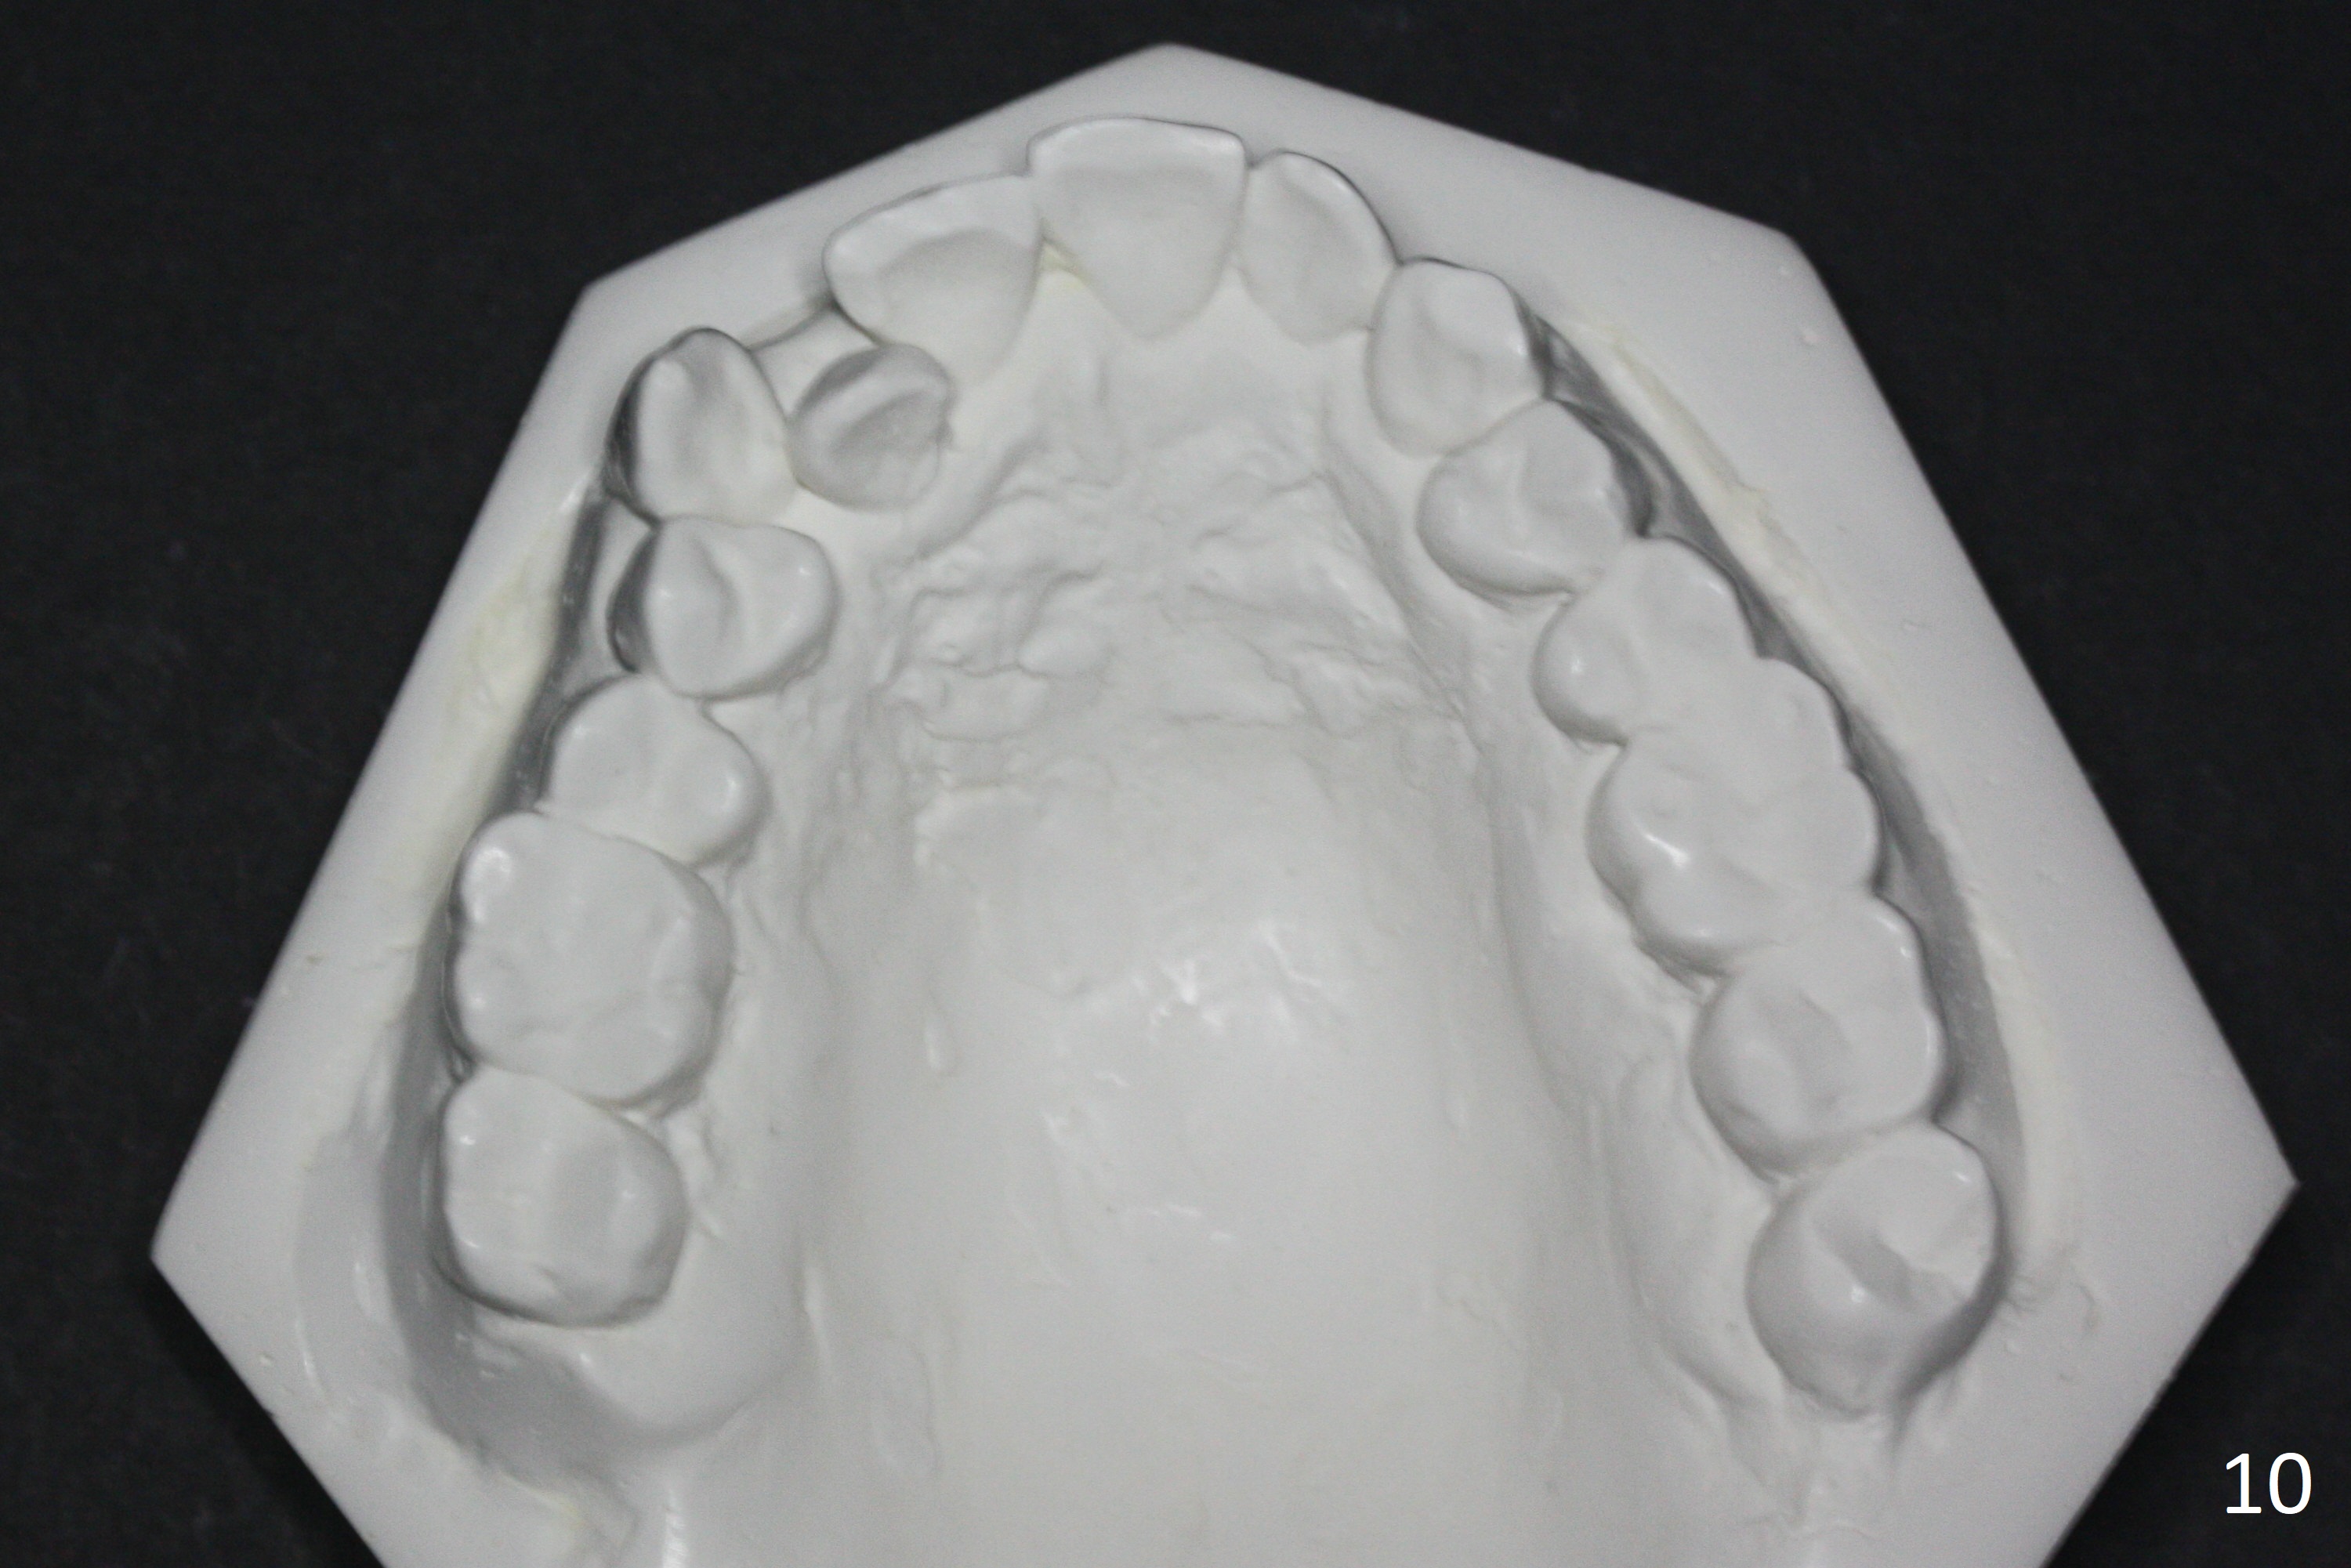

Enough Space For Crowding After Extraction? A 47-year-old man requests orthodontic treatment following SRP in other office (Fig.1-11). For severe crowding and midline shifting, extraction of four of the 1st bicuspids is imminent. Is it enough? To answer the question, model surgery is performed (Fig.12-16). 1st visit: periodontal maintenance, orthodontic consent (emphasizing oral hygiene) extract 4s and possibly L8s and separators. The beauty of this vist is that after local anesthesia and extraction including L8s, it is painless and easy to remove calculus from the proximal surfaces of the neighboring teeth. It is much easier to place separators after extraction. It is expected that there is no gingival erythema when the patient returns for bracketing. Take photos of UR3, similar to Fig.3. Molar banding is also anticipated to be easy with separator placement after extraction. Return to Ortho Cases Xin Wei, DDS, PhD, MS 1st edition 11/23/2017, last revision 04/28/2019